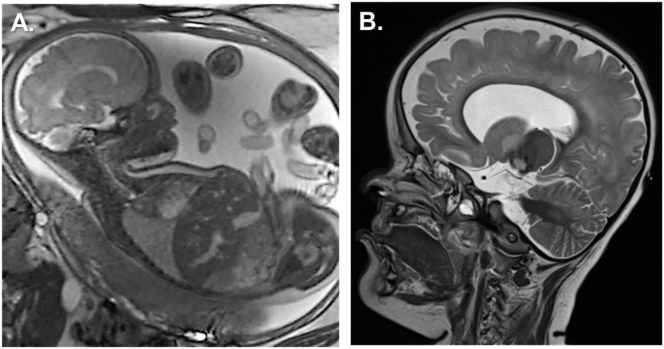

Case presentation: Here, we present a child's case diagnosed with bilateral anophthalmia at 33 weeks of gestation. The newborn was delivered vaginally with a RAX-gene-linked syndrome. Besides craniofacial malformations (bilateral anophthalmia, craniofacial hypoplasia, bilateral cleft lip), the female child had severe endocrine dysfunction (congenital hypopituitarism and diabetes insipidus) postnatal that required specialised monitoring and clinical management. Our case study reports a novel homozygous autosomal recessive non-sense mutation (c.106G>T; p.Glu36Ter) of the RAX gene. This is the first description of this pathogenic gene variant in the literature.